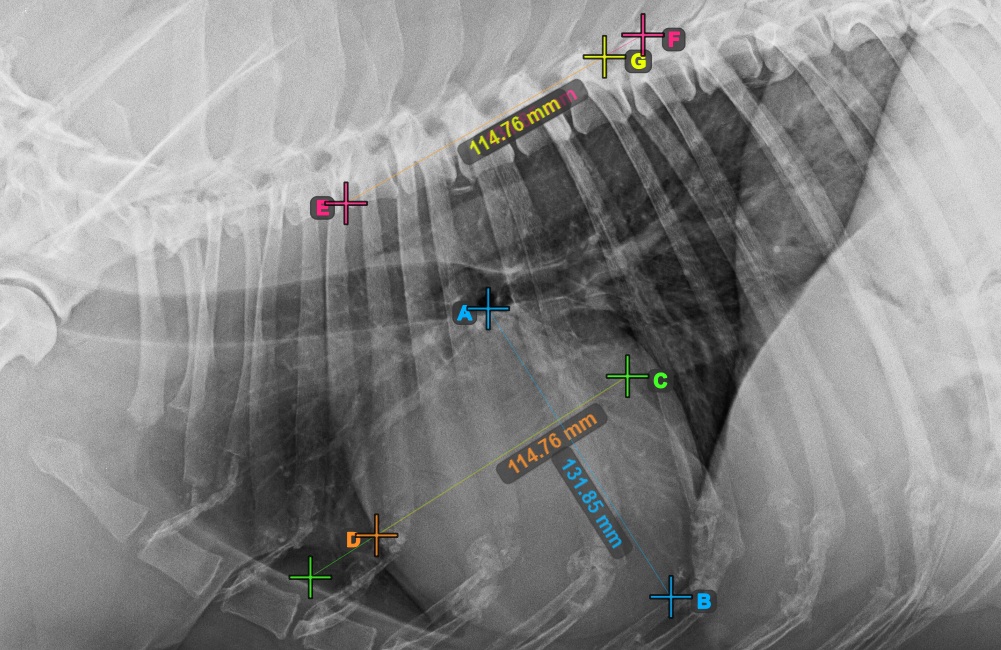

Identify the beginning of the T4 vertebra (the fourth vertebral body of the spine), counting from the initial point of the spine. Mark the beginning of the T4 vertebrae to continue the measurement. The software will draw lines from the marked point along the spine. The length of the lines depends on the measured long and short axes of the heart.

The image below represents the typical placement of the point at the beginning of the fourth vertebral body of the spine.